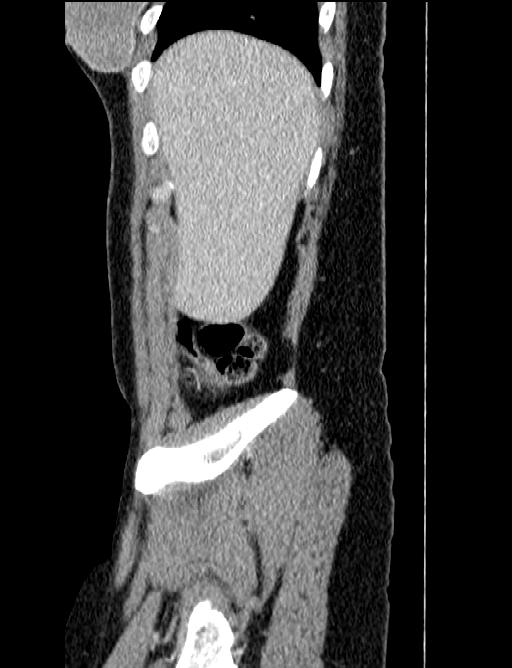

44 year old female with a long medical history. Undergone repeated surgeries for prox. 30 years. Not always fully understood what the purpose has been or expected outcome from all the procedures.

MRI August 2010.

Diagnose: There is no evidence to suspect that this patient may have an active phase of disease.